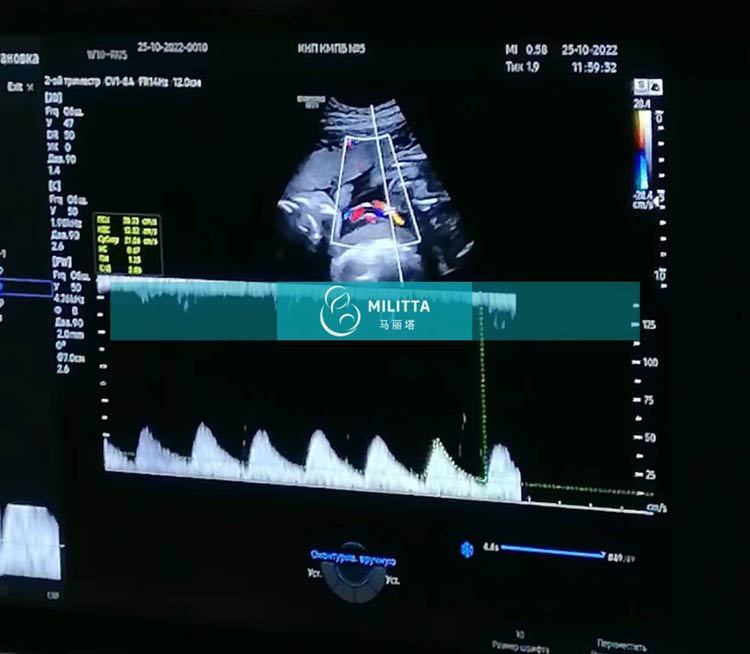

乌克兰试管孕妇做的是做四维彩超,宝宝正常健康发育中

这位乌克兰试管孕妇做的是做四维彩超,可以看到宝宝正常健康发育中。